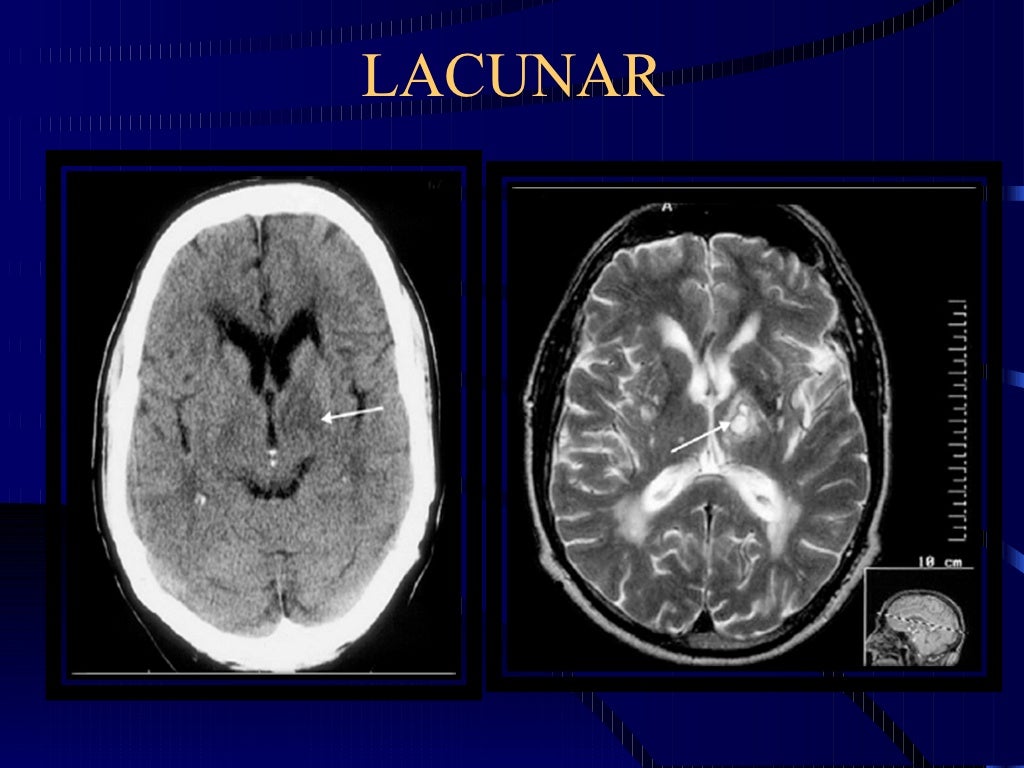

El concepto de infarto lacunar (IL), es un tipo de accidente cerebrovascular isquémico caracterizado por lesiones de pequeño diámetro, no mayor de 15 mm, producido por oclusión en el territorio de distribución de las arterias perforantes del cerebro (lenticuloestriada, tálamoperforante o paramediana del tronco cerebral).

Los infartos lacunares afectan en general a las arterias perforantes, que son vasos de 0,1-0,5 mm de diámetro, que se originan en la 1.ª porción de la arteria basilar, arterias cerebrales anterior, media y posterior, que irrigan estructuras profundas en cerebro y tronco. En general, los clásicos factores de riesgo cardiovascular, pero con mayor impacto la hipertensión, produce necrosis fibrinoide y lipohialinosis, que son claves en la fisiopatología de este tipo de lesiones. Otros factores, como disecciones arteriales, embolias atrio arteriales, cardioembolías o procesos ateromatosos son potenciales causas de la formación de lagunas.